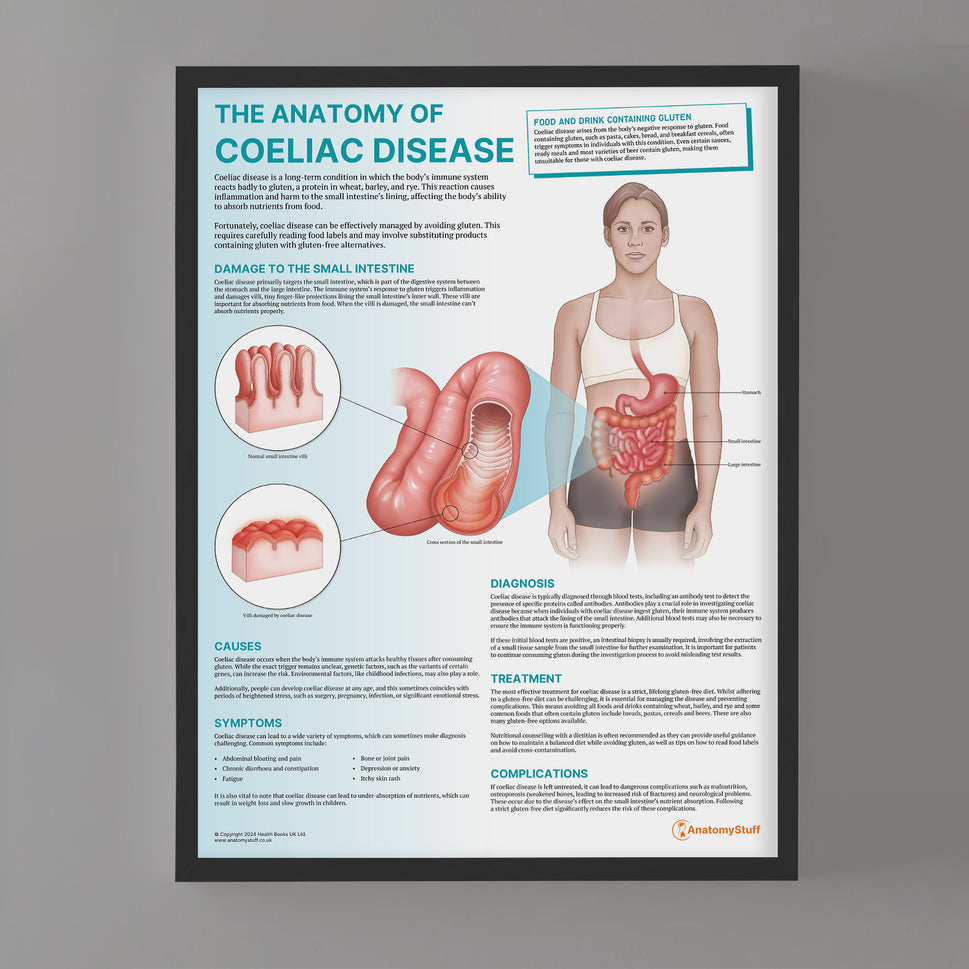

Enhance medical education with our collection of digestive system anatomical models including the stomach, liver, gallbladder, pancreas & colon models. Discover the anatomy of healthy organs as well as common gastrointestinal diseases such as stomach ulcers, gallstones and liver cirrhosis. Our digestive system anatomy posters are ideal for study and patient education.

At AnatomyStuff we stock a diverse range of digestive system anatomical models to suit your training needs. From budget models and affordable medical education posters to highly advanced 3D printed bowel models, you can transform medical training and patient education. As well as our own exclusive collection, we are proud resellers of 3B Scientific, Anatomy Lab, Denoyer-Geppert Science Company, ESP Models, Erler Zimmer and GPI Anatomicals. Explore our exclusive collection of digestive system anatomy charts, posters, fine art prints and digital anatomy study guides. Discover the anatomy of key organs like the liver, stomach, pancreas and bowel as well as the pathophysiology of common conditions like peptic ulcer disease, coeliac disease, IBD and much more. We have anatomy posters suitable for school children all the way up to medical degree level. From a liver anatomy poster to a digital study guide all about common GI disorders, find exactly what you need right here to enhance medical training and patient education.